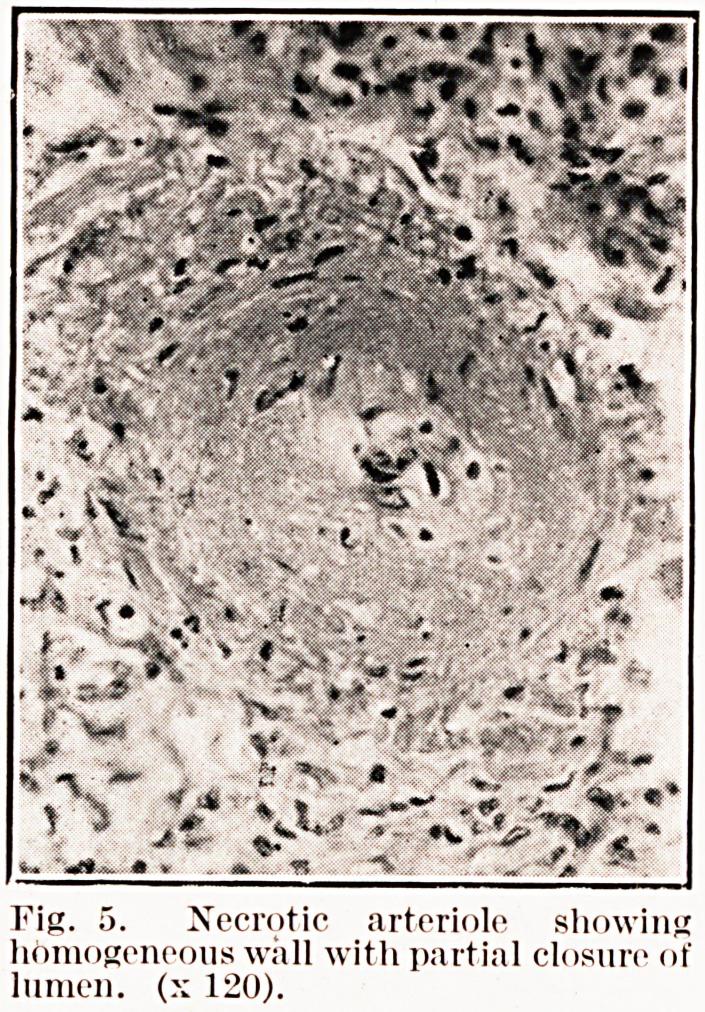

The rheumatic lung; report of two cases.

Glasgow Med J. 1947 May;28(5):127-33.